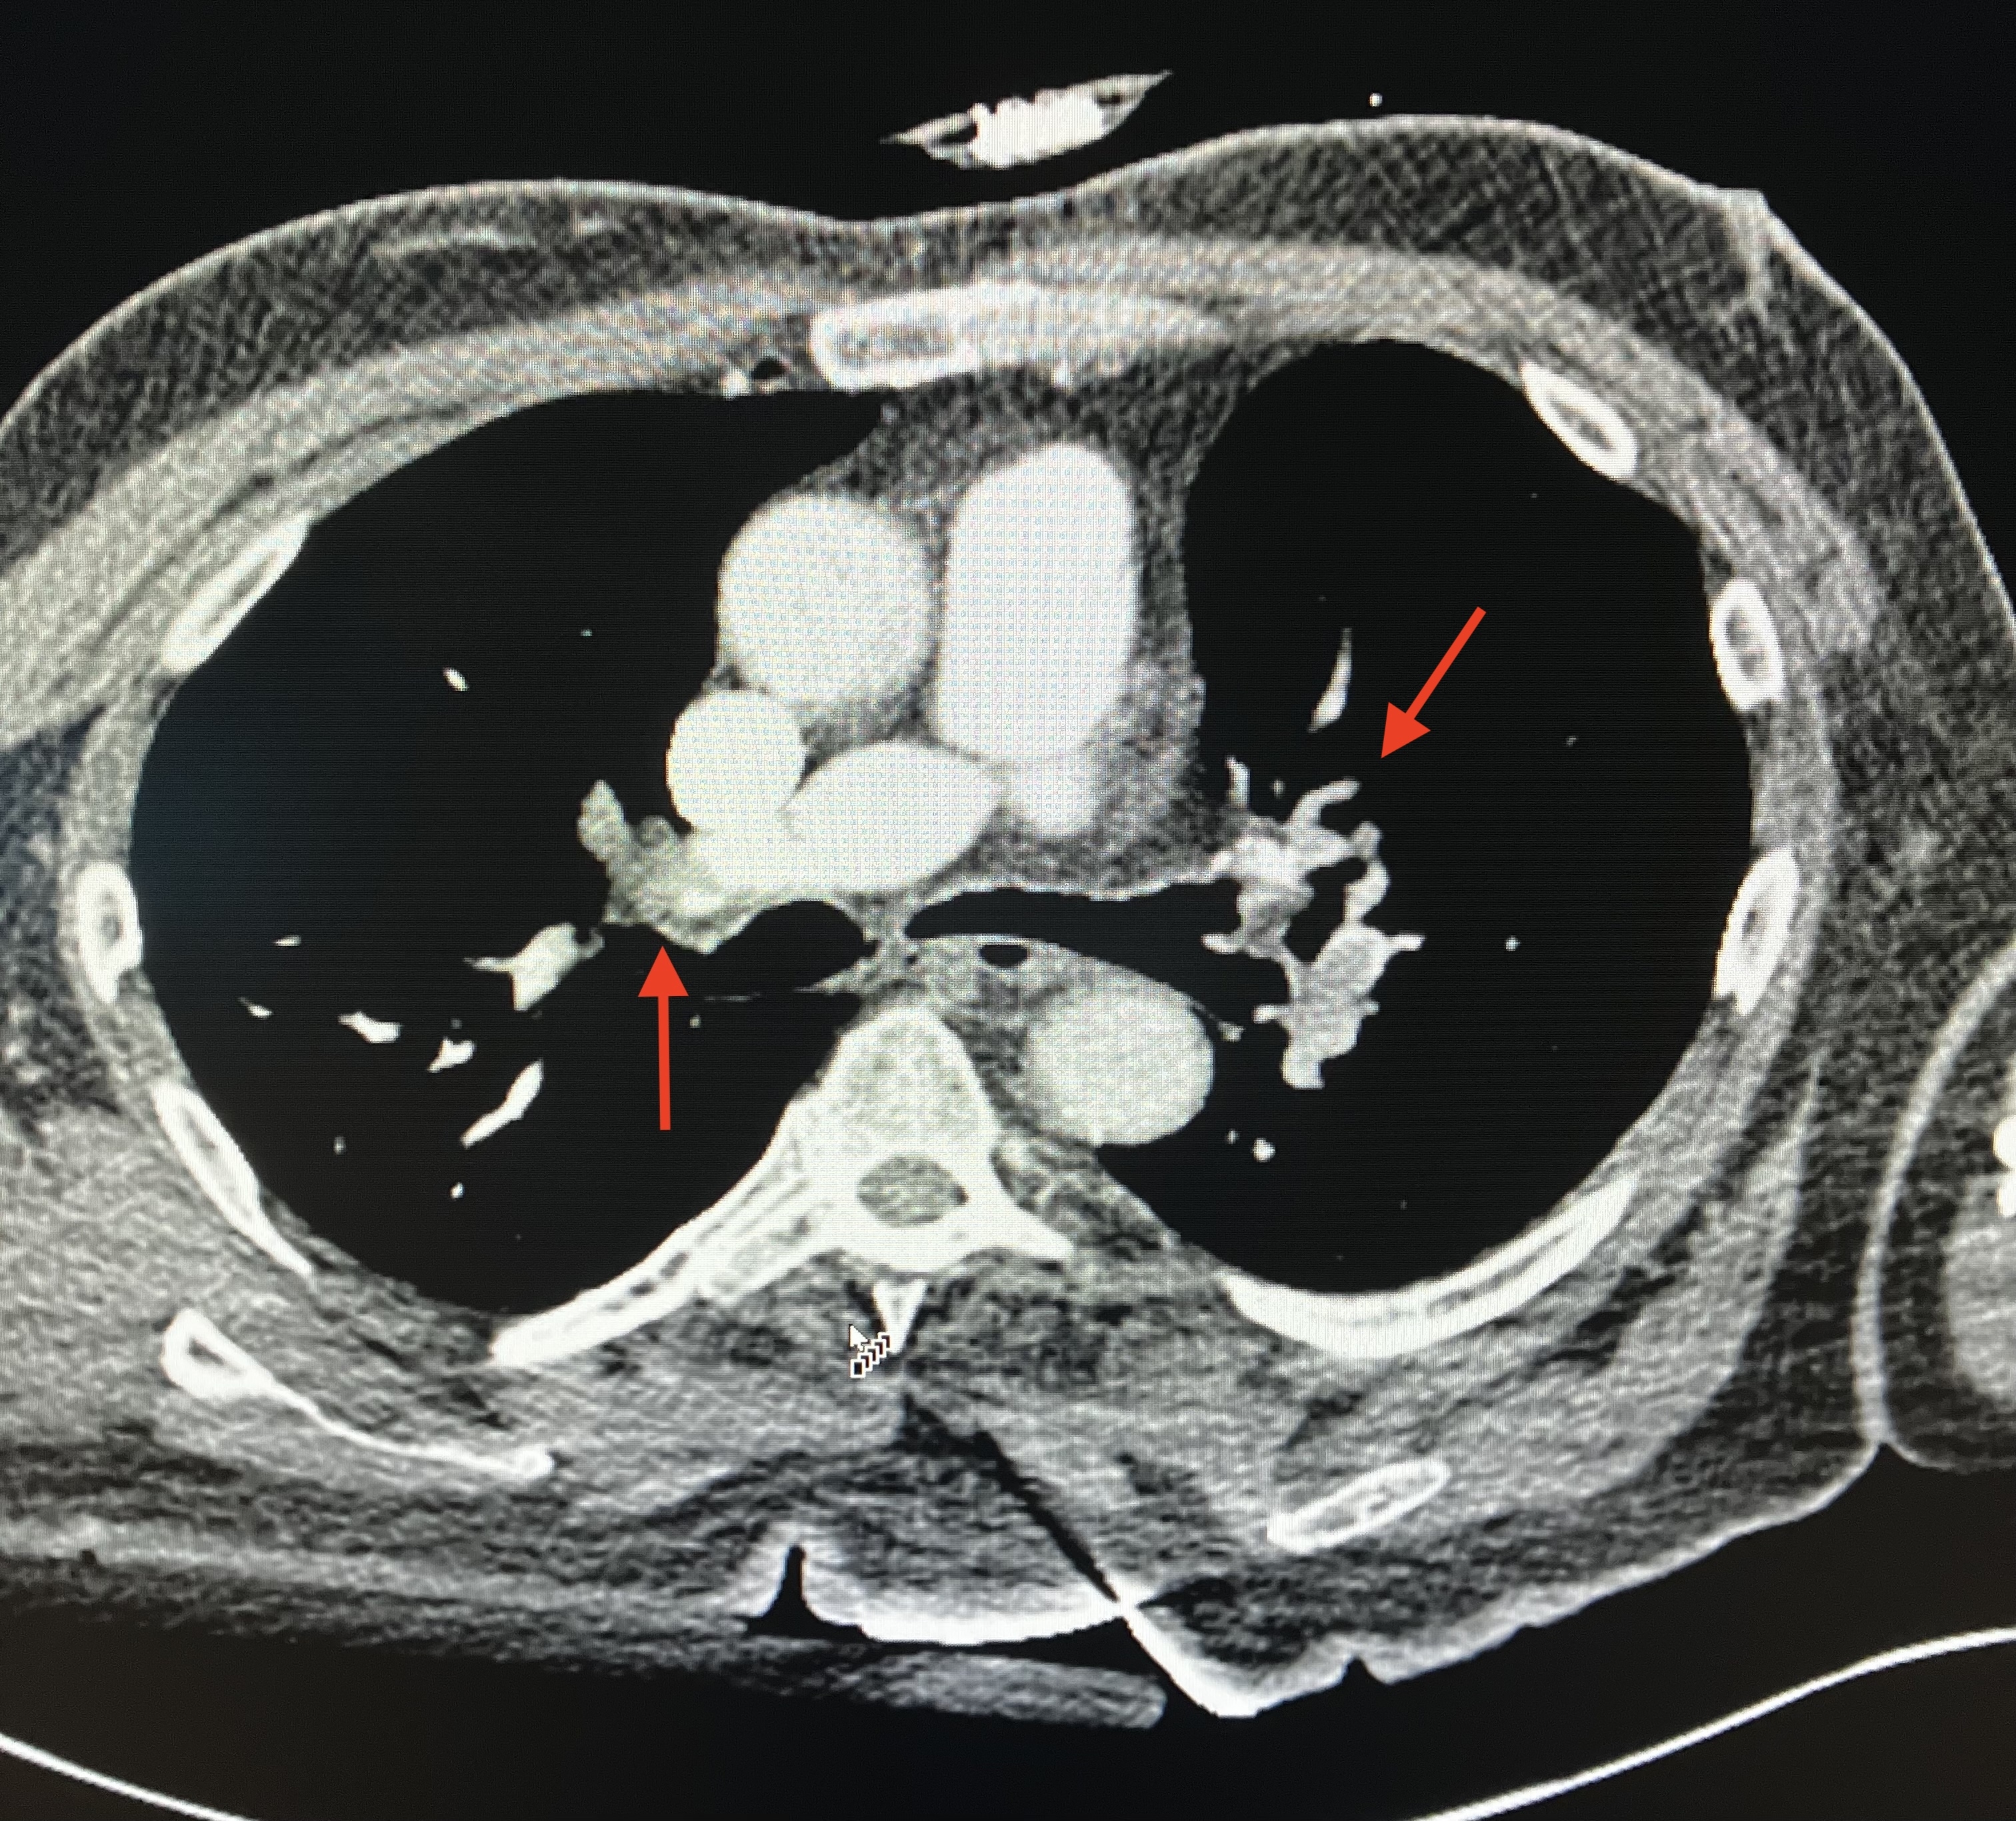

CT angiography revealed bilateral pulmonary emboli (PE) with right heart strain. Emergent coronary angiography showed occlusion of the left circumflex artery, which was successfully stented. Pulmonary thrombectomy was performed the following morning with effective clot extraction. Despite aggressive management, the patient developed progressive renal and hepatic failure with worsening lactic acidosis. Abdominal CT revealed extensive bowel ischemia due to acute mesenteric embolism. Transthoracic echocardiography with bubble study confirmed the presence of a patent foramen ovale with right-to-left shunting, consistent with paradoxical embolism.